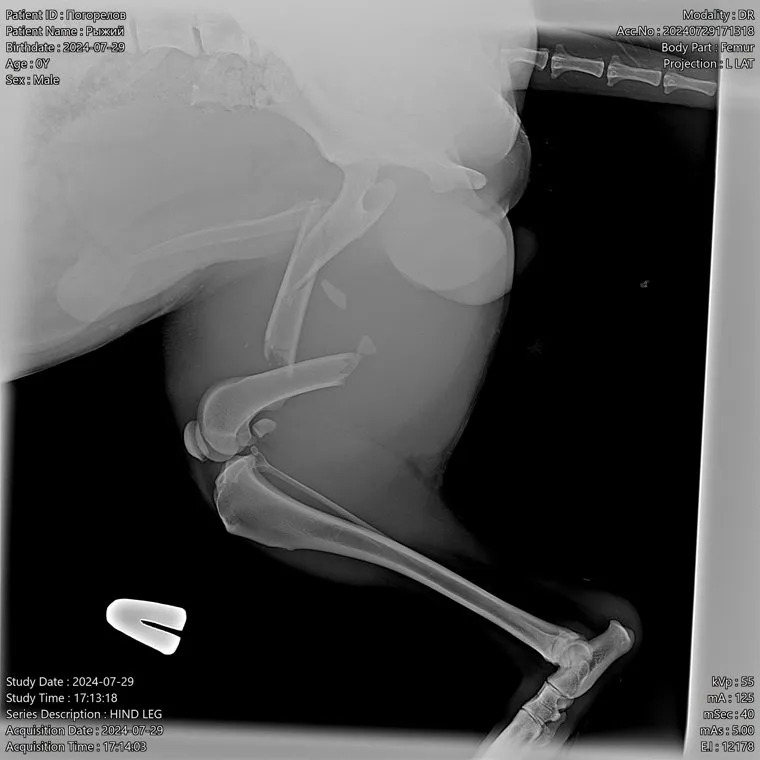

Что касается беспородной собаки по кличке Малыш, то у нее очень сложный оскольчатый перелом со смещением. Он сейчас в клинике форда «Маленькая жизнь». Фонд откроет сбор средств и будет договариваться с клиниками чтоб Малыша прооперировали. Реабилитация после операции с применением аппарата Илизарова займет несколько месяцев.

Рентгеновский снимок показал у собаки сложный перелом, требующий операции и восстановления с применением технологии остеосинтеза